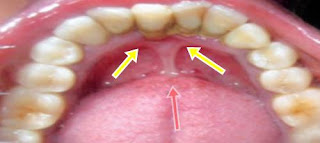

Diş eti çekilmesi neden olur nasıl geçer ve belirtileri nelerdir. Diş eti çekilmesi dişleri saran diş eti dokusunun dişi veya diş kökünü açığa çıkartarak geri çekilmesidir diş eti çekilmesi sonucunda dişler ve diş eti çizgisi arasında cepler veya boşluklar oluşur. Dis temizligi denilince sadece dislerin kirlenen renklerini acmak degil dis taslarinizin da temizlenmesi demektir 6 ayda bir temizlik detertraj dis etlerinizi sihhatli olmasini saglar gunde en az 2 kerede dis ve dis eti fircalanmasi sart dis temizligi yaparken agri olmaz bu durum diş etlerinin çekilmesine neden olmaz. Tedavi edilmez ise sağlam dişlerin kaybedilmesine kadar gider.

Diş eti dokularına gelen kan desteğini kısarak ve o bölgede sürekli tahrişe neden olarak diş eti çekilmesine neden olur. Estetik diş hekimliğine artan ilgi ve talepler diş eti çekilmesi tedavilerinde farklı periodontal plastik cerrahi tekniklerinin gelişmesine öncülük etmiştir. Diş eti çekilmesi yaşayanların dişleri gittikçe daha uzun görünür diş hassasiyeti artar tedavi ihmal edilmezse iltihaplanma ve ağız kokusu problemleri ortaya çıkabilir. Diş eti çekilmesinin ilk olarak neden olduğunu bilmek belirtilerini takip etmek.

Bu boşluklara hastalığa neden olabilecek bakteriler kolayca birikebilir. Günümüz yaygın ağız hastalıklarının başında diş çekilmesi gelir. Diş eti çekilmesi diş etlerinde kanama ile başlar. Dişi çene kemiğine bağlayan destek dokuların zarar görmesi sonucu diş etinin dişin kök tarafına doğru uzaklaşmasıdır nedeni diş eti iltihabı gibi hastalıklar olabildiği gibi sigara kullanımı hatalı diş fırçalama diş gıcırdatma hormonal değişimler de diş eti çekilmesine neden olur.